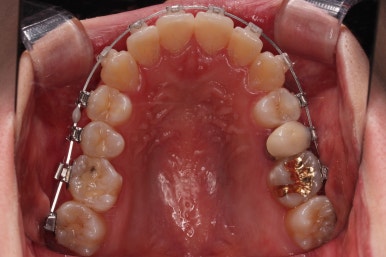

악궁확장을 먼저 시행합니다.

아랫니에 비해서 윗니의 악궁의 폭이 좁기 때문에 가로폭을 먼저 개선합니다.

이번 환자분은 성인이긴 했지만 미니스크류 없는 일반 타입의 악궁확장장치로 시도하기로 했습니다.

악궁확장 이후, 유지단계 동안 확장의 유지에 필요한 치아를 제외하고는 브라켓을 부착하게 됩니다.

이번 환자분이 선택한 장치는 엠파워 클리어라고 하는 자가결찰 세라믹 장치인데요.